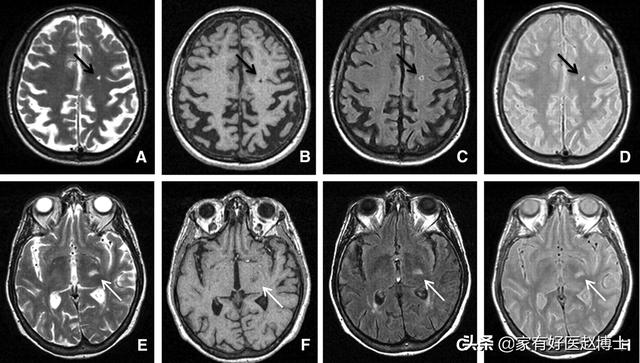

第五个要说的是“腔隙性脑梗塞”,这在颅脑CT或磁共振检查当中是中老年朋友们比较常见的一种异常结果。

腔隙性脑梗塞不同于大面积脑梗塞,很多时候医生并不会给与特殊的治疗意见。但是,腔隙性脑梗塞被认为与大脑里小动脉的内皮功能障碍密切相关,因此,也属于血管老化的一种表现。